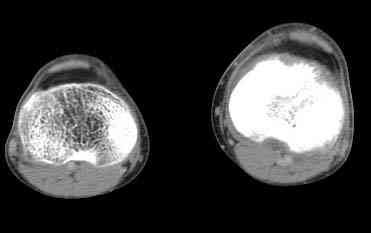

важаемые коллеги! Поступил больной 22 лет. Болен с января 2006 - появились боли в области верхнейтрети голени. При первичном осмотре в поликлинике был заподозрен первично-хронический остеомиелит - осмотрен гнойным хирургом - произведена биосия . Заключение - хондросаркома. Осмотрен онкологом - с учетом характера опухоли - химиотерапия, лучевое лечение не показано. Предложена либо ампутация, либо решение вопроса о возможности выполнения органосохраняющей операции. При обращении к нам произведена сцинтиграфия скелета - зоны гиперфиксации РФП: верхняя треть голени- 960%, нижняя треть бедра - 380%, Дистальный метафиз голени и затылочная область - 140%. В легких - метастазов нет. Произведена КТ (картинки в приложении). Учитывая абсолютную нестыковку рентгенологических и морфологических данных повторно биопсия. Выявлено, что первичная биопсия выполнялась из поверхностной параоссальной зоны - там локализованы хрящеподобные массы, далее очень плотная кость без хрящевых участков - биоптат взят фрезой с большим трудом. Морфологического заключения пока нет. Хотелось бы узнать Ваши варианты диагноза и соответственно тактику.